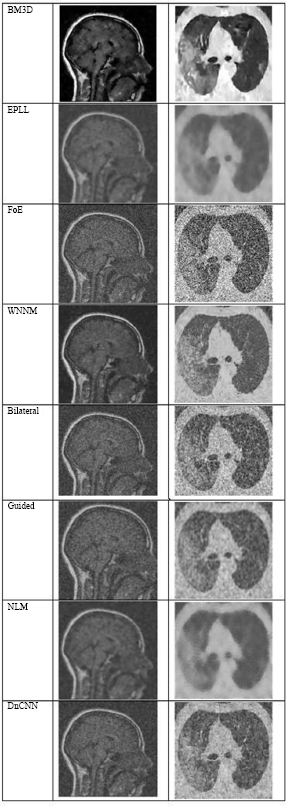

Fig. (4) shows the results at a noise variance of 0.01, where it has been observed that all algorithms produce clear images, except for the Guided algorithm.

Fig. (5) shows the results at a noise variance of 0.05, where it has been observed that the BM3D, EPLL, and WNNM algorithms produce clearer images compared to other algorithms. NLM and DnCNN also perform well, but not as well as the above-mentioned three algorithms.

Fig. (4).

The output of different algorithms at a noise variance of 0.01.

Fig. (5).

The output of different algorithms at a noise variance of 0.05.

Fig. (6) shows the results at a noise variance of 0.09, where it is observed that the BM3D, EPLL, and WNNM algorithms produce clearer images compared to other algorithms. Another algorithm, DnCNN, also performs well, but not so well as the above-mentioned three algorithms.

Fig. (6).

The output of different algorithms at noise variance 0.09.

Fig. (7) shows the results at a noise variance of 0.5, where it has been observed that all the algorithms produce blurred images, except for the BM3D algorithm. However, the results of the BM3D algorithm are not so satisfactory. As a result, it has been observed that at a noise variance of 0.5, none of the algorithms performed well.

Fig. (7).

The output of different algorithms at Noise Variance 0.50.